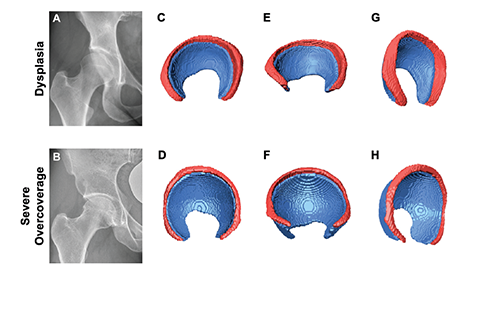

Contribution of Labrum and Cartilage to Joint Surface in Different Hip Deformities An Automatic Deep Learning–Based 3-Dimensional Magnetic Resonance Imaging Analysis

This study paves the way for a more in-depth understanding of the underlying pathomechanism and a reliable 3D analysis of the hip joint that can be indicative for surgical decision-making in patients with hip deformities.

Meier et al., Am J Sports Med. 2025